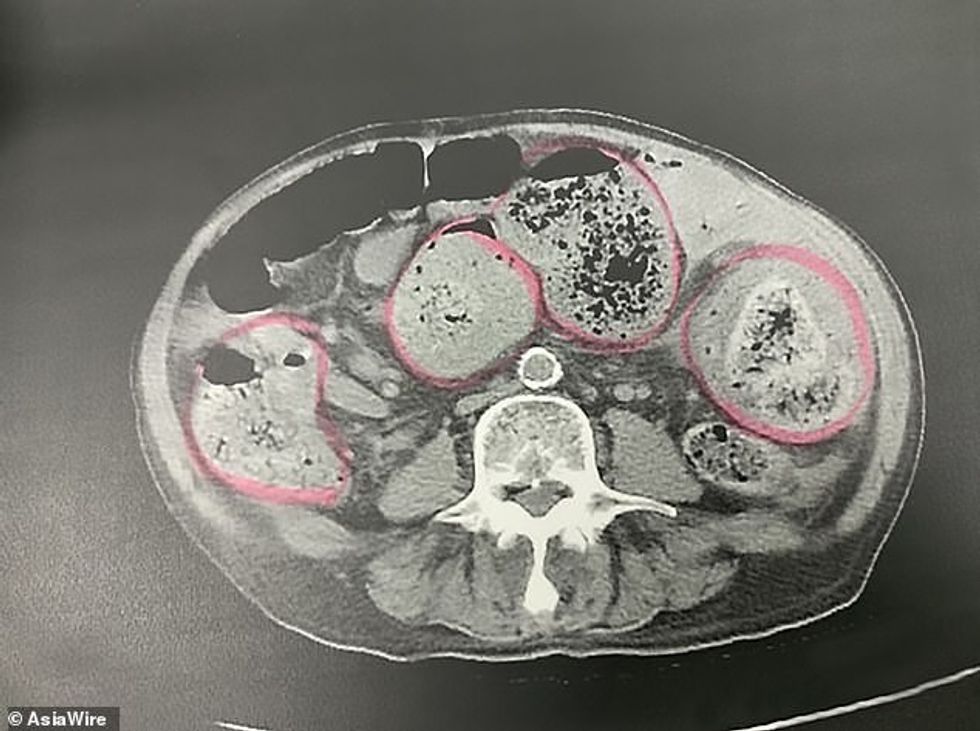

Mjekët bënë ekzaminimet dhe gjetën fekale të ngurtësuara rreth 30 centimetra në stomakun e tij, raportojnë mediat lokale.

Kirurgët e spitalit "Chung-Ho Memorial" i detyruan ti heqin një pjesë të zorrës për të përmirësuar gjendjen shëndetësore të të moshuarit. Shpesh herë, mjekët shpjegojnë se ngjarje të tilla u ndodhin të gjithë personave që nuk balancojnë dietën me shumëllojshmëri ushqimesh.